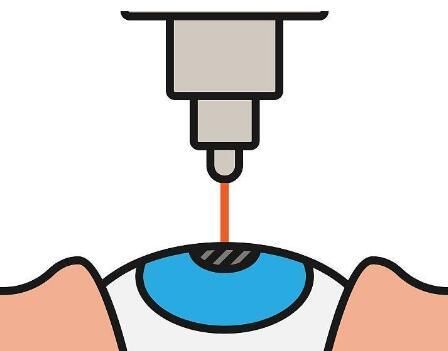

第四步:切割病变角膜

医生会在患者的眼部进行消毒和覆盖无菌布。然后,医生会使用角膜切割器或角膜缝线在病变的角膜上切割一个圆形开口。切割的大小和位置取决于病变的范围和需要。